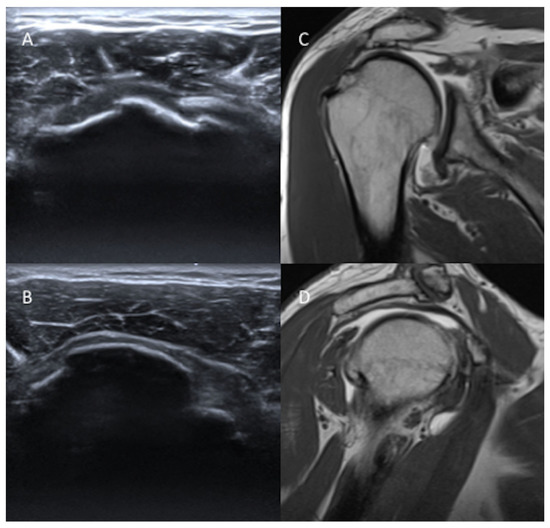

2. Materials and Methods

2.2. US Protocol

2.3. MRA Protocol

2.4. Analysis of US and MRA Images